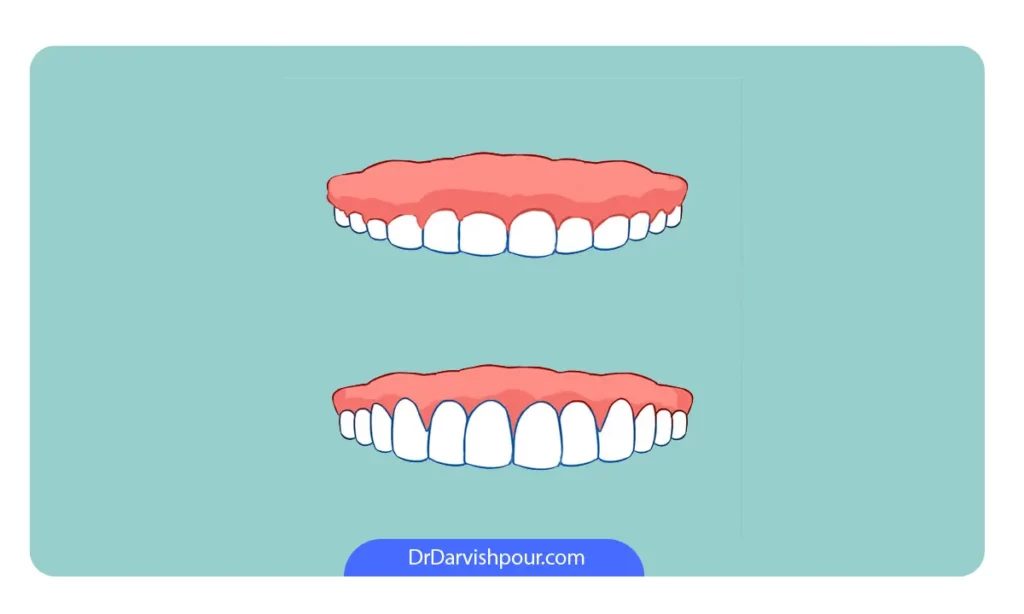

7. عمل جراحی زیبایی لثه یا کانتورینگ لثه (Gum contouring surgery)

کانتورینگ لثه یک روش کم تهاجم است که شامل تغییر شکل جزئی، ایمن و دقیق خط لثه می شود. با برداشتن بافت اضافی لثه که روی دندان ها را گرفته، خط لثه عقب تر می رود و طول تاج دندان نیز افزایش می یابد. این روش به بهبود زیبایی و هماهنگی لبخند کمک می کند.

اصلاح خط لثه فواید زیادی دارد که به بهبود سلامت دهان و دندان و افزایش زیبایی لبخند منجر میشود. اولین و مهم ترین فایده این روش، کاهش احتمال ابتلا به بیماری های لثه مانند التهاب و ورم لثه است. با برداشتن بافت اضافی لثه، فضای مناسبی برای تجمع پلاک و باکتری ها باقی نمی ماند و این امر باعث می شود که احتمال بروز عفونت های لثه ای کاهش یابد.

یکی دیگر از فواید اصلاح خط لثه، بهبود ظاهر لبخند و افزایش اعتماد به نفس فرد است. با اصلاح خط لثه، دندانها بلندتر و لبخند زیباتر به نظر میرسند. این تغییرات ظاهری میتوانند تأثیر زیادی بر روی روحیه و اعتماد به نفس فرد داشته باشند. به این ترتیب، اصلاح خط لثه نه تنها از لحاظ بهداشتی بلکه از لحاظ زیبایی نیز دارای اهمیت ویژهای است.